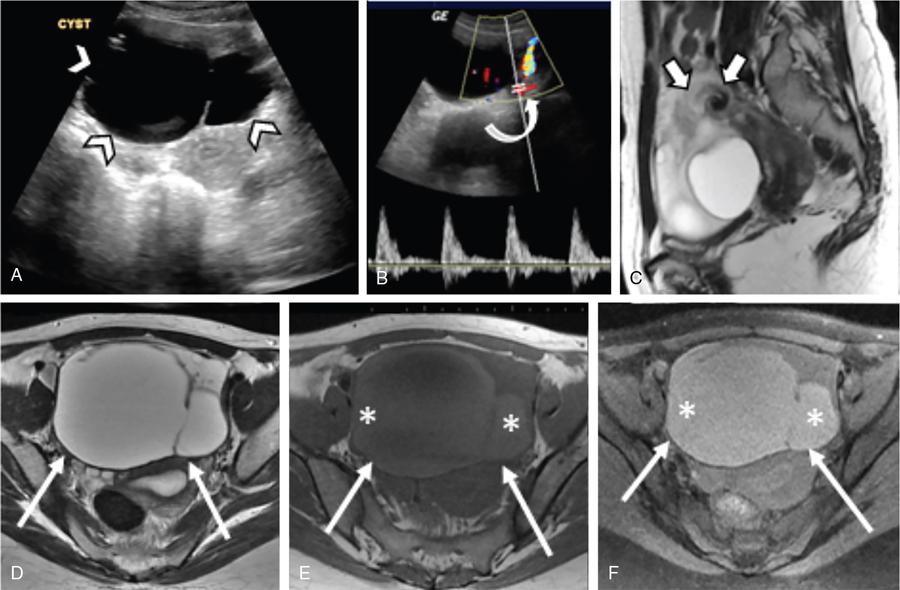

Fig. 11.16.1.7 Benign mature cystic teratoma with torsion: A 30-year-old woman presented with episodes of lower abdominal pain and vomiting. (A) USG showed a complex right ovarian cyst (arrowheads) with septae. (B) No intralesional vascularity noted on Doppler examination. (C) Coronal and (D) axial T2WI, (E) axial TIWI and (F) FST1WI showed a complex right ovarian cyst, with an area of signal intensities consistent with fat (asterisk). (C) Thickened and twisted pedicle with the pathognomic ‘whirlpool’ appearance is also noted (thick arrows). Laparoscopic right ovariotomy with excision of the tumour was done.

Fig. 11.16.1.8 Benign seromucinous cystic tumour with torsion in a 31-year-old woman with complaints of acute lower abdominal pain. (A) Grey-scale ultrasound shows a large cyst with thin septae anterior to the uterus (arrowheads). (B) Colour flow Doppler reveals arterial flow in the pedicle with no flow within the cyst (curved arrow). (C) Sagittal T2WI shows the classical ‘whirlpool’ sign of the twisted pedicle (short thick arrows). (D) Axial T2WI, (E) T1WI and (F) FST1WI demonstrates the midline anterior location of the cyst (thin arrows), with the contents appearing hyperintense on T1WI and FST1WI (asterisks). Emergency laparoscopic cystectomy was done with a final diagnosis of Benign seromucinous tumour.